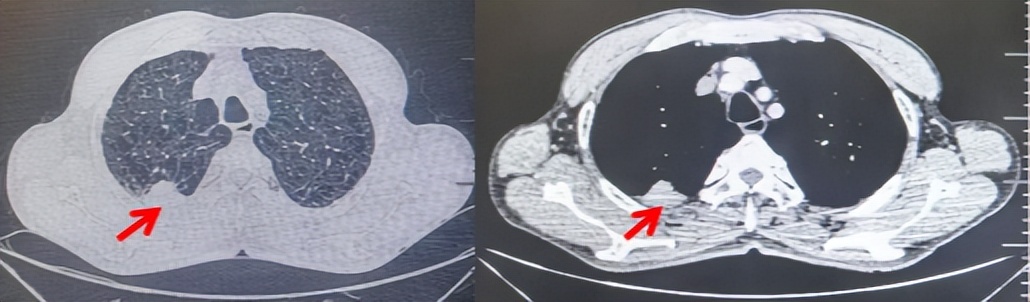

71岁男性,高血压病史20年,口服药物治疗,无糖尿病、心脏病等基础疾病,吸烟史50年,20支/天,已戒1年余,无饮酒史,无肿瘤家族史。2023.11因咳嗽、咳痰行胸CT检查:左肺下叶占位性病变,大小约12mmx8mm(如图5)。2023.11.20行“单孔胸腔镜左肺中下叶切除、肺门及纵隔淋巴结清扫、胸膜粘连松解术”;术后病理:(左肺下叶)结合免疫组化鳞状细胞癌(中、低分化),局部见脉管内癌栓,未见确切神经侵犯,(气管切缘)净。(淋巴结)未见转移癌0/19(4组0/1;5组0/1;6组0/2;7组0/1;9组0/1;10组0/2;11组0/3;12组0/2;13组0/2;14组0/4)。术后分期pT1bN0M0 IA期,术后定期复查。

2024.09.12复查胸部CT示左侧胸膜结节,大者约为27mmx13mm,考虑转移可能性大,纵隔淋巴结增大,恶性?(如图6)。患者行胸膜穿刺活检取病理,结果示(胸膜)结合免疫组化,支持鳞状细胞癌,PD-L1(克隆号28-8)TPS约20%。分期为rT0N2bM1a IVA期,DFS为10个月。2024.09.24起行替雷利珠单抗联合紫杉醇+卡铂方案治疗4周期,复查胸CT评效SD(如图7)。后患者因脑梗塞停止治疗,于综合医院就诊,后未返院复查及治疗。